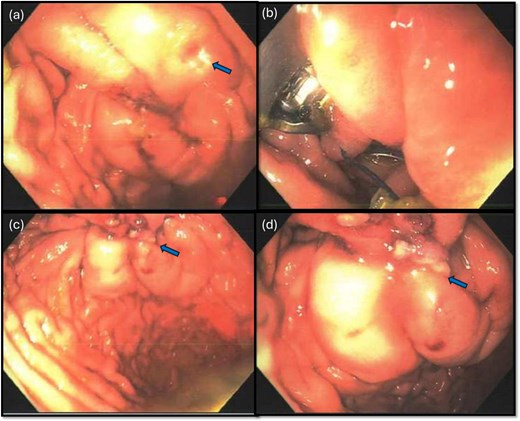

A leak test was then performed by submerging the repair site under saline and endoscopically insufflating the stomach; no bubbling was noted, indicating a successful seal. The repair was reinforced with an omental patch, secured laparoscopically with a 2–0 silk suture (Fig. 4). A single drain was left in the abdomen, remaining fluid was suctioned. Endoscopic biopsies of the stomach and duodenum were obtained, and a nasogastric tube was placed.

Following endoscopic closure, a leak test performed under water (a) did not demonstrate any bubbling after gastric insufflation with air. Photos (b–d) demonstrate performance of a graham patch with a redundant lip of omentum over the endoscopically closed perforation.